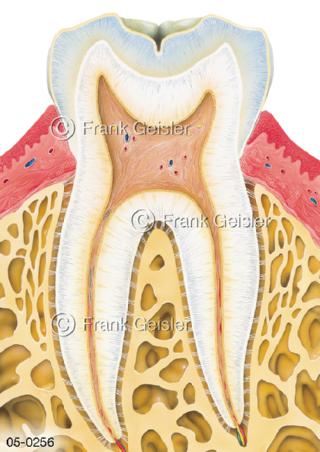

Bildergalerie Skelettsystem

Bilder zum Skelettsystem zeigen die Stützstruktur des menschlichen Körpers, die Knochen, eine besonders harte Form des Bindegewebes und Stützgewebes, welche das menschliche Skelett bildet, die Knochen des Stammes, der Extremitäten sowie der Gelenke